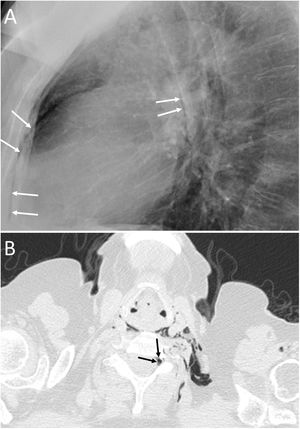

Transdiaphragmatic intercostal hernia consists of herniation of abdominal contents through the thoracic wall through a diaphragmatic defect. It is most common after trauma, but it can also appear after coughing attacks or massage.32 Chest X-ray and CT can identify rib fractures, when present, with increased intercostal space secondary to them and the presence of intestinal loops in the chest wall (Fig. 14). The treatment of choice will be surgery through simultaneous repair of the diaphragmatic and intercostal defects.32

A 55-year-old man with a mass on the right chest wall of more than two years of evolution. A) Computed tomography (multiplanar reconstruction in coronal and sagittal planes) revealed a right transdiaphragmatic intercostal hernia with colon and abdominal fat (white arrows). C) Multiplanar reconstruction in the sagittal plane enabled identification of the diaphragmatic defect (white asterisks). B) The 3D (sagittal plane) showed fracture calluses in the lateral arches of the eighth and ninth right ribs (white arrows) with widening of the intercostal space (white asterisk).